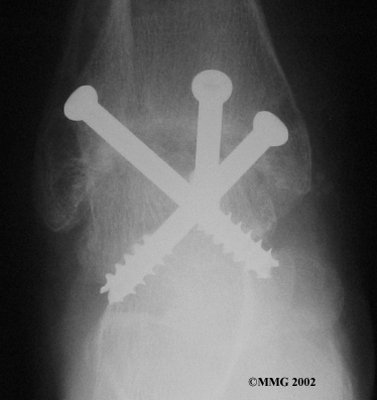

It is important when the surfaces are removed that the angles of the cut surfaces are correct. When the tibia is brought against the talus, the foot should be at a right angle to the lower leg. Once the cuts are made the bones must be held in place while they fuse. This can be done using large metal screws and metal plates if necessary. The screws are usually under the skin and are not removed unless they begin to rub and cause pain.

Inserting the screws

After ankle fusion, the physical therapists at FYZICAL Ellenton can help you learn to walk smoothly and without a limp. Although time needed for recovery varies among patients, an ankle brace will typically replace your cast after eight to 12 weeks. Your surgeon will take X-rays frequently to see if the bones are fusing together. You will probably need to use crutches during the time you wear the cast. As the fusion grows stronger, you will begin to put more weight on your foot when walking.